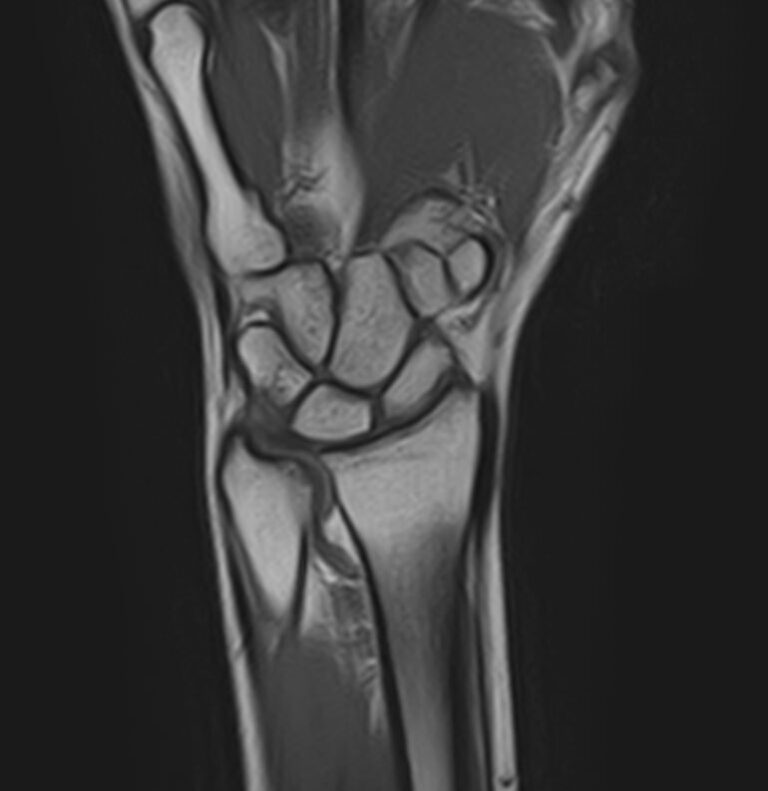

МРТ является современным высокоинформативным неинвазивным и при этом безопасным методом исследования, который позволяет детально визуализировать состояние всех структур лучезапястного сустава, включая дистальные отделы лучевой и локтевой костей, хрящей, сухожилий, нервов и окружающих мягких тканей.

В клинике «Доступная медицина» исследование проводится на новейшем высокопольном томографе экспертного класса TOSHIBA VANTAGE TITAN 1,5 Тесла, который делает послойное сканирование исследуемой области в различных плоскостях с шагом от 1 мм и в дальнейшем преобразует полученные данные в трехмерные изображения. Результаты МРТ позволяют выявлять заболевания лучезапястного сустава на начальных стадиях и назначать своевременное лечение.

МРТ лучезапястного сустава позволяет выявить следующие патологии:

• Заболевания связочно-мышечного аппарата: гигромы запястья, флегмоны.

• Артриты. В отличие от КТ или рентгенодиагностики, МРТ позволит обследовать все структуры сустава, повреждающиеся при данных заболеваниях — синовиальную сумку, кисты, краевые костные узуры. Это особенно актуально на ранних стадиях заболевания, когда при рентгенологическом обследовании нет четких изменений.

• Остеомиелиты — МРТ дает возможность провести раннюю и точную диагностику заболевания, оценить внутри и внекостные поражения.

• Туннельный синдром запястья — заболевание неврологической природы, которое возникает из-за сдавления срединного нерва костями, связками или сухожилиями, располагающимися в области запястья.

• Опухолевые новообразования — МРТ позволит дифференцировать степень злокачественности новообразования, определить степень его распространения и взаимодействия с окружающими тканями.